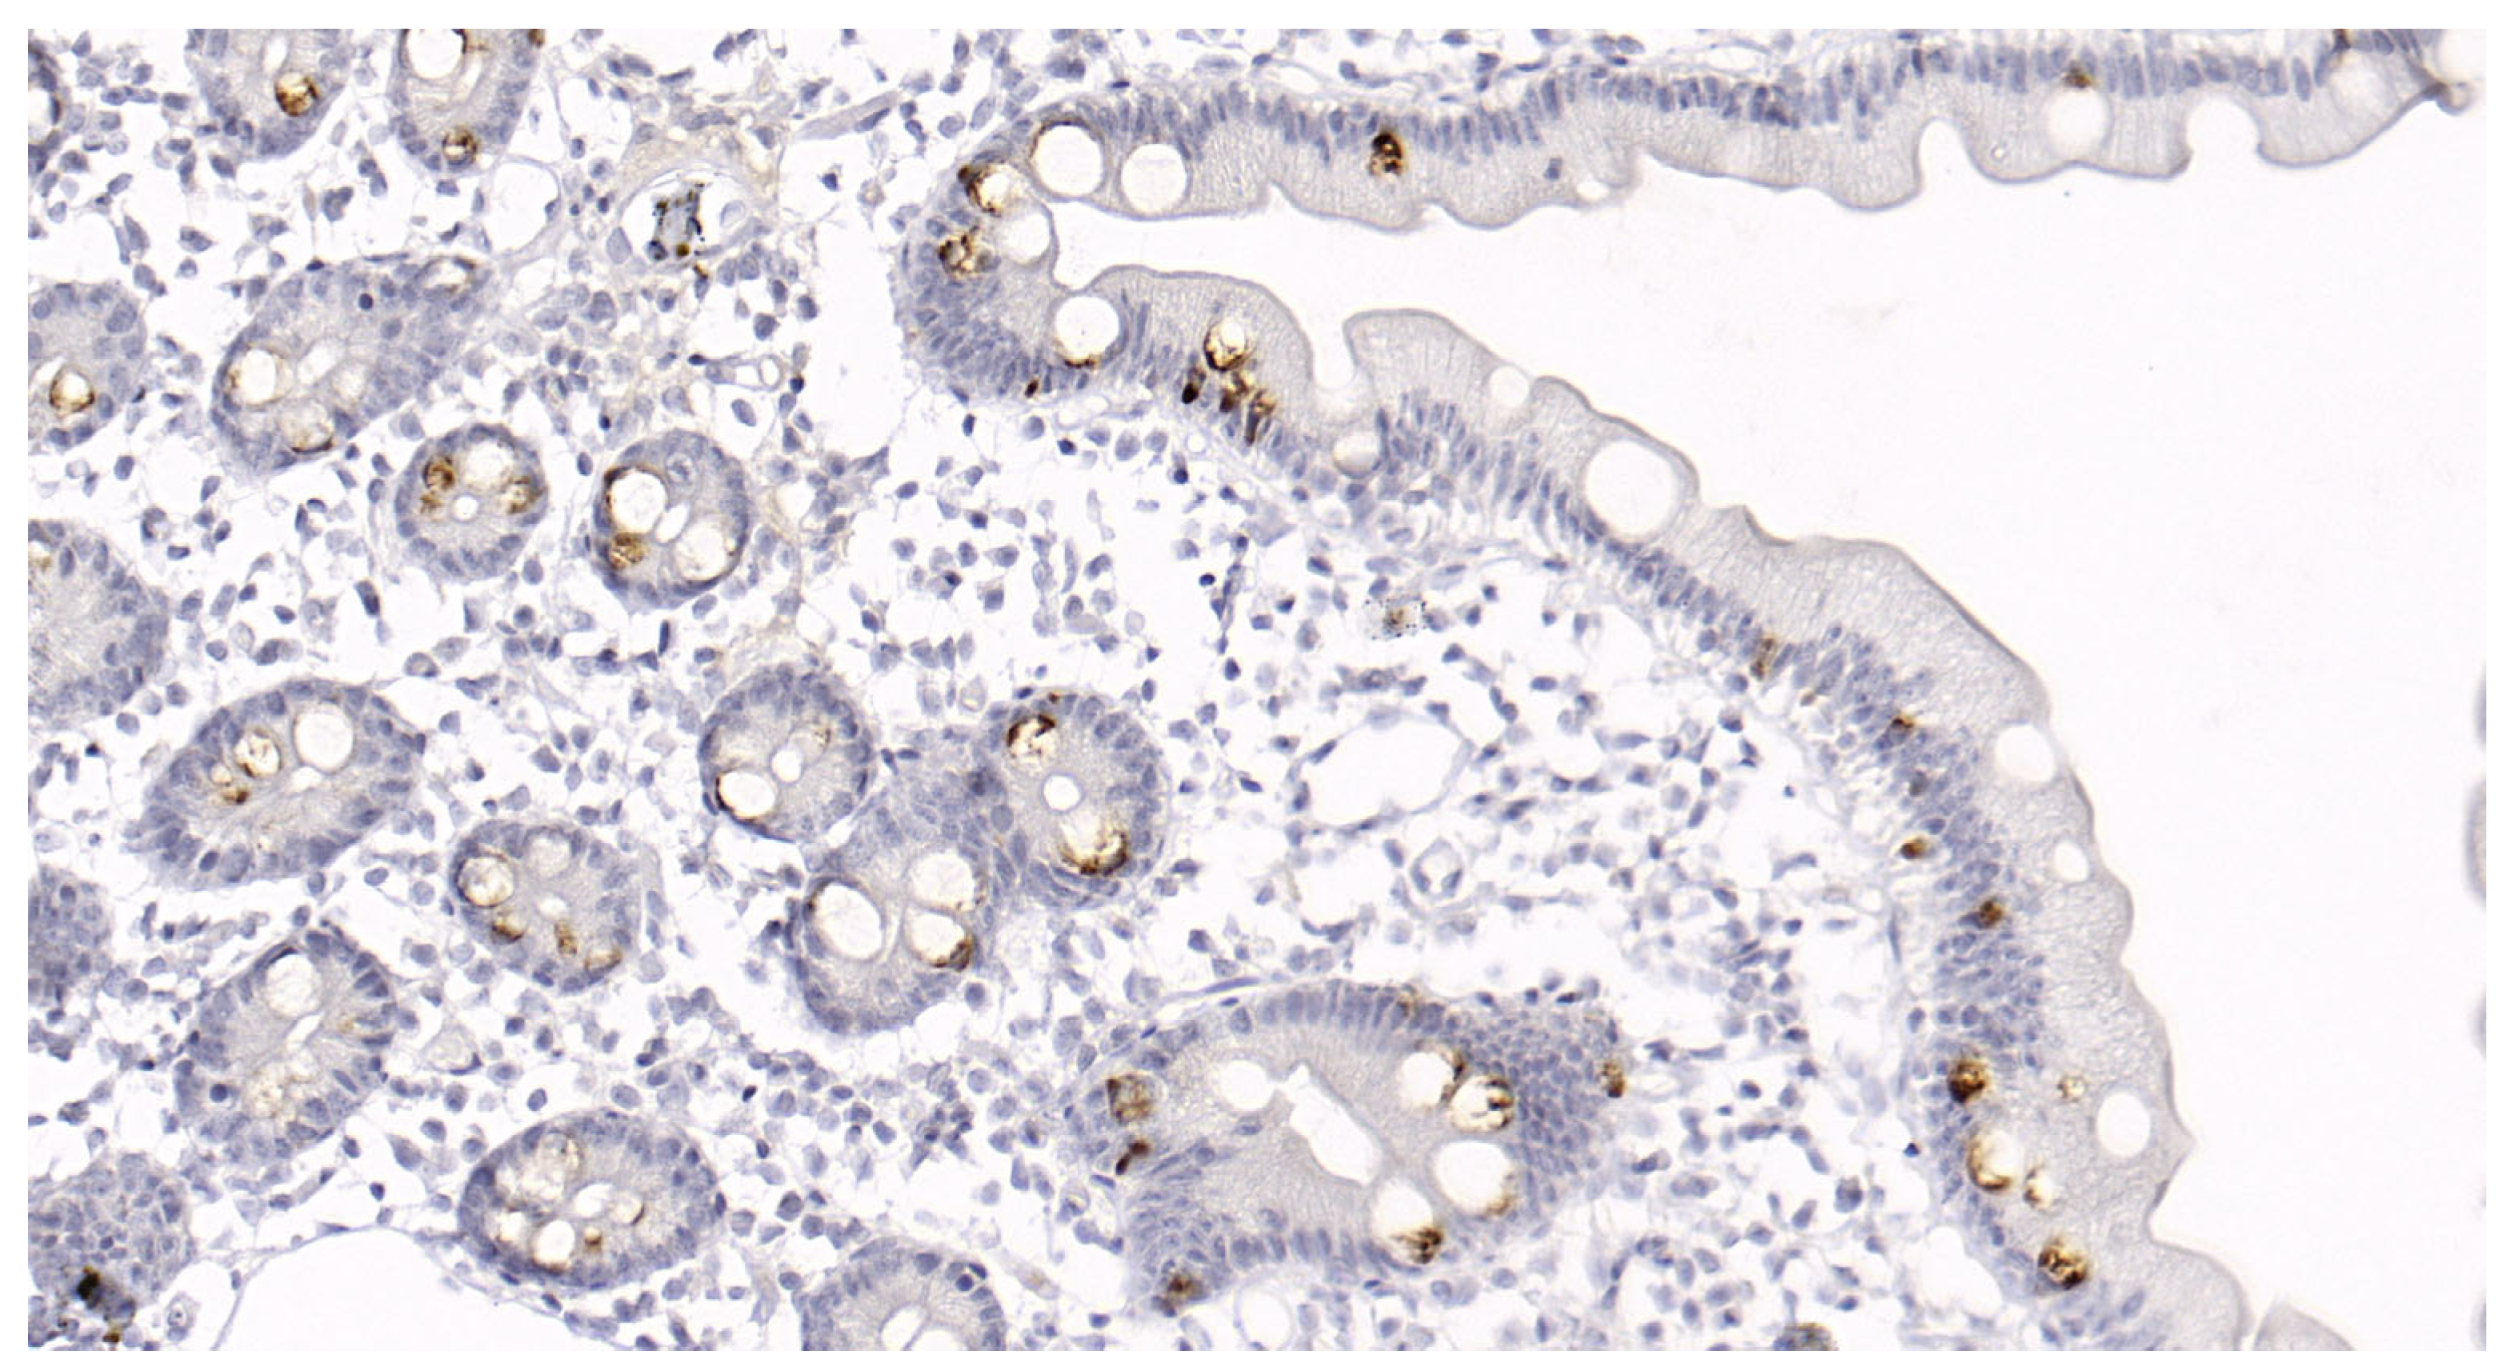

2.4. Study Protocol

Figure 1. Biopsy of the duodenal mucosa of a patient with diarrhea-predominant irritable bowel syndrome and functional dyspepsia overlap. Magnification ×400. Hematoxylin-eosin staining. The patient sample shows lymphocytic infiltration ( ) (11 to 15 lymphocytes per 100 epithelial cells, corresponding to Group 3) and an increased number of eosinophils (*) (mean number is 6.8 in the standard field of view).